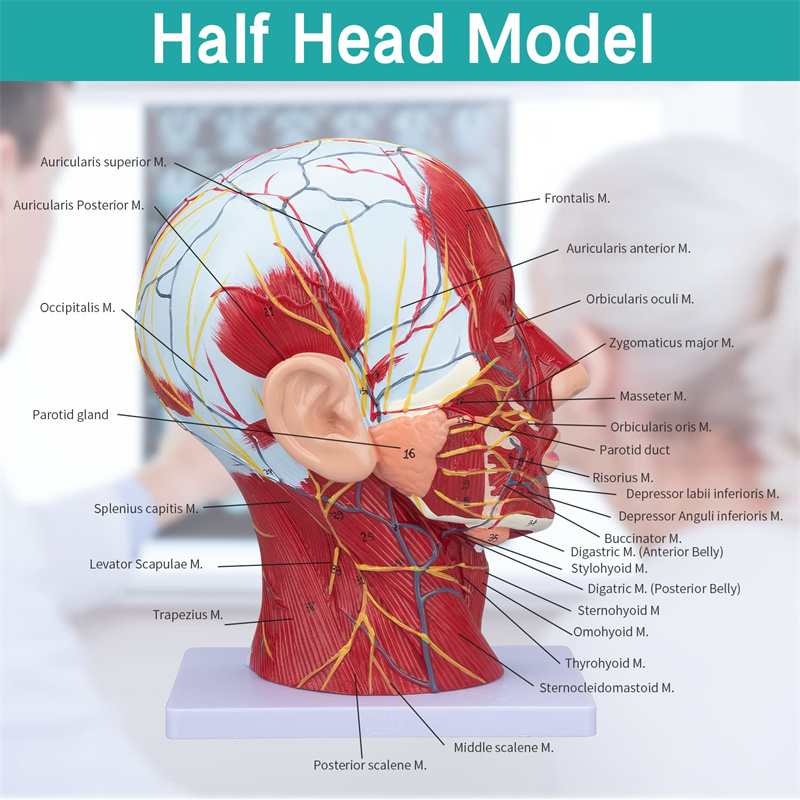

| Izici | Imodeli ikhombisa i-morphology yendawo yezinhlangothi zangaphakathi nezingaphandle zengxenye ye-Median Sagittal yekhanda nentamo, kanye nezinhlaka zemithambo yegazi nezinzwa, futhi kunezingxenye ezingama-84 ezibonisa izibonakaliso zizonke. |

【Imodeli ye-Neurovascular yemisipha ekhethekile enemininingwane eminingi, izinombolo ezimakwe kakhulu, izindlebe ezivinjelwe, zijulisa ukuqonda kwemisipha engaphezulu, imikhumbi, izinzwa kanye nezinhlaka zangaphakathi zekhanda nentamo. I-Red-artery, i-Blue-Vein, i-Yellow-Nerve.

Izici 【Izici】 Kubonisa izicubu ezingezinhle zobuso obudaluliwe; Imithambo yegazi engekho emthethweni nezinzwa zobuso ne-scalp; Izakhiwo ezingaphakathi ze-Parotid Gland & Upper Respiratory Tract; isakhiwo sesigaba se-sagittal somgogodla wesibeletho.

Le modeli ikhombisa imininingwane yekhanda leNhloko yeNhloko yeNhloko ne-Mid sagittal yomuntu. kufaka phakathi okuphezulu

izicubu zobuso obudaluliwe; Imithambo yegazi engekho emthethweni nezinzwa zobuso nesikhumba; Izakhiwo ezingaphakathi

ye-parotid gland nepheshana lokuphefumula elingaphezulu; isakhiwo sesigaba se-sagittal somgogodla wesibeletho.

Le modeli ikhombise i-morphology yendawo yezingxenye zekhanda nentamo yekhanda nentamo kanye nezinhlaka zayo ze-vascular nezinzwa, ezinazo ingqikithi yezinkomba eziyi-100.

Le modeli iyinhloko enkulu yemvelo nemodeli ye-neurovascular yemisipha eyindilinga, isakhi esingu-1, ekhombisa imininingwane yekhanda lelungelo lomuntu kanye nentamo kanye nengxenye ye-Median Sagittal, okubandakanya imisipha engemihle yobuso, imithambo ephakeme yobuso obukhulu bobuso kanye nesikhumba, izinzwa nokwakheka kwempilo kwe-parotid gland kanye nepheshana lokuphefumula elingaphezulu, kanye nesakhiwo seSigaba se-sagittal somgogodla wesibeletho